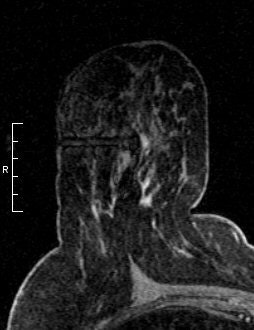

![]() The ability to offer MR-guided biopsy is key to any screening program. In this case, MR-guided biopsy helped identify a 5-mm invasive ductal cancer and high-grade solid-type in situ carcinoma. The patient elected mastectomy.

Image courtesy of Dr. Bruce Porter, |

She and other breast imaging experts recommend that the availability of MR-guided intervention should be a mandatory prerequisite for offering breast MR imaging. In 2001, lack of access to MR-guided biopsy was identified as the single major reason for the delayed adoption of breast MRI in clinical practice.

Technology and equipment innovations of the past seven years have minimized this roadblock. If a facility is not equipped to perform an MRI-guided biopsy, it should partner with a local facility that is.